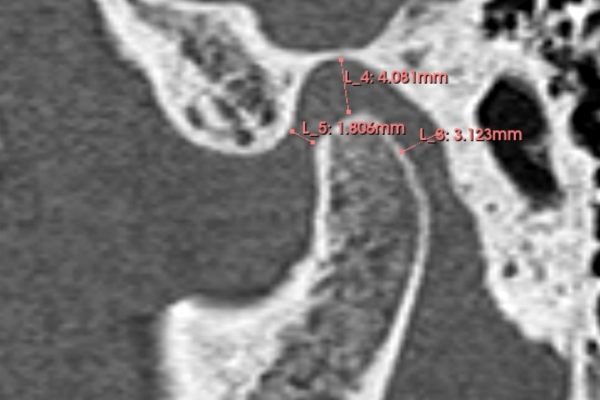

En la actualidad, la tecnología en odontología ha permitido realizar estos tratamientos de manera más eficiente y cómoda para el paciente. La técnica del Clon digital o Paciente Virtual, por ejemplo, permite obtener un modelo digital dinámico del paciente, lo que permite diseñar todo el tratamiento digitalmente y utilizar bibliotecas de dientes naturales para obtener un resultado estético y funcionalmente óptimo. Gracias a esta técnica, se pueden realizar tratamientos en menos citas y con mayor comodidad para el paciente.